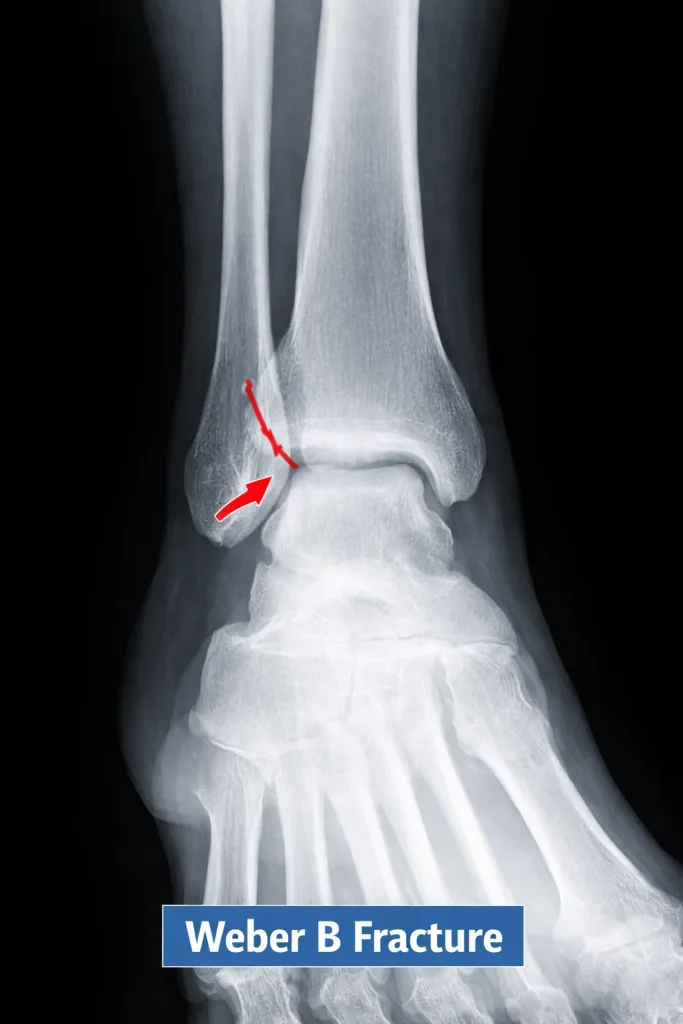

Weber B Fracture

A Weber B fracture occurs at the level of the syndesmosis. This is the most common Weber type. Stability varies depending on ligament involvement.

Radiology Features

- Oblique fracture line

- Fracture at the joint level

- Possible medial malleolus involvement

Weber B fractures require careful assessment because some are stable while others are unstable.

Stable vs Unstable Weber B Fracture

This is the most critical distinction in Weber B management, and it is what every treating surgeon must determine before choosing between conservative and surgical care.

Stable Weber B fracture:

- Syndesmosis remains intact

- No widening of the medial clear space

- No talar shift on stress X-ray

- The deltoid ligament is uninjured

- Can be treated with a cast or boot

Unstable Weber B fracture:

- Syndesmosis is disrupted

- Medial clear space widened (>4 mm on mortise view)

- Talar shift present

- The deltoid ligament may be torn

- Requires surgical fixation

The gravity stress test, or external rotation stress X-ray, is routinely used to assess stability in borderline Weber B cases. If talar shift appears under stress, the fracture is considered unstable, and surgery is recommended.